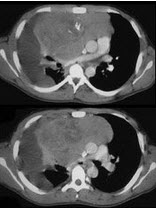

男,28岁,咳嗽,咯血,消瘦盗汗1个月余,影像学检查如图。最可能的诊断为( )

A:类风湿肺炎

B:右上肺周围型肺癌

C:右上肺浸润型肺结核

D:右上肺炎性假瘤

E:右上肺曲真菌感染